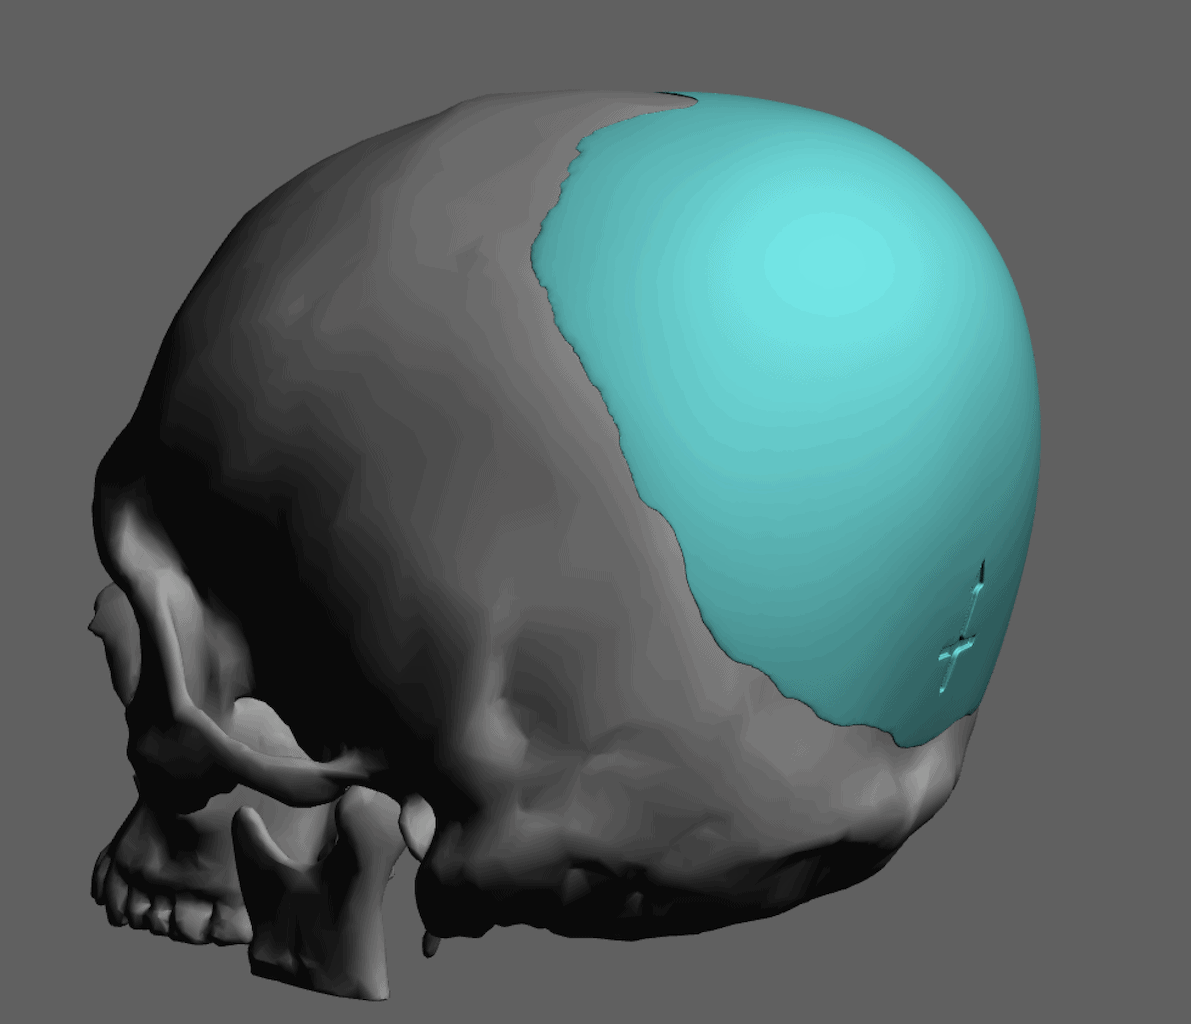

Placement of custom extended forehead-temporal implants through incisions in the crease behind the ear. (he had a prior back of head skull implant which is green in the implant designs and which the head widening implants partially covered it)

Desire for change of head shape from front view form an inverted V shape to a rounder and wider head shape.

Placement of custom extended forehead-temporal implants through incisions in the crease behind the ear. (he had a prior back of head skull implant which is green in the implant designs and which the head widening implants partially covered it)